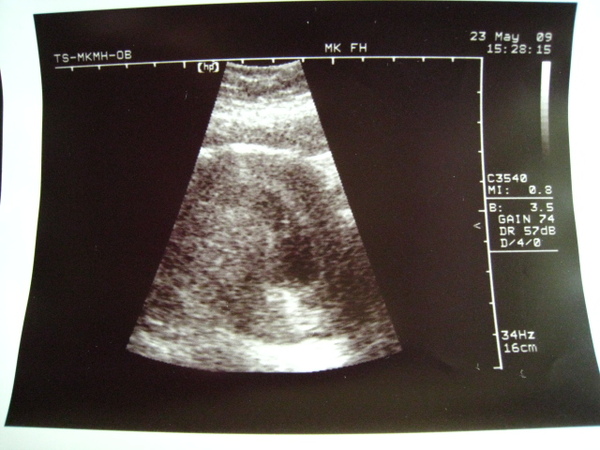

2009.05.23 淡水馬偕產檢 (不滿意決定換婦幼醫院) 7W_4D